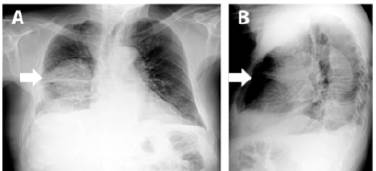

Mediante tomografía computarizada de tórax contrastada (Figura 3) se encontraron: en ápices pulmonares, bulas subpleurales; a nivel parahiliar derecho, una masa de bordes irregulares de 70x75mm; adyacente a esta, otra masa de 53x45mm, y en segmento apical del lóbulo inferior del pulmón derecho, otra masa de 65x61mm de características similares, acompañada de derrame pleural derecho libre de moderado volumen y con espacio pleural izquierdo libre.

Tomografía computarizada de tórax contrastada.

Figura 3: Tomografía computarizada de tórax contrastada.

Fuente: Documentos obtenidos durante la realización del estudio.